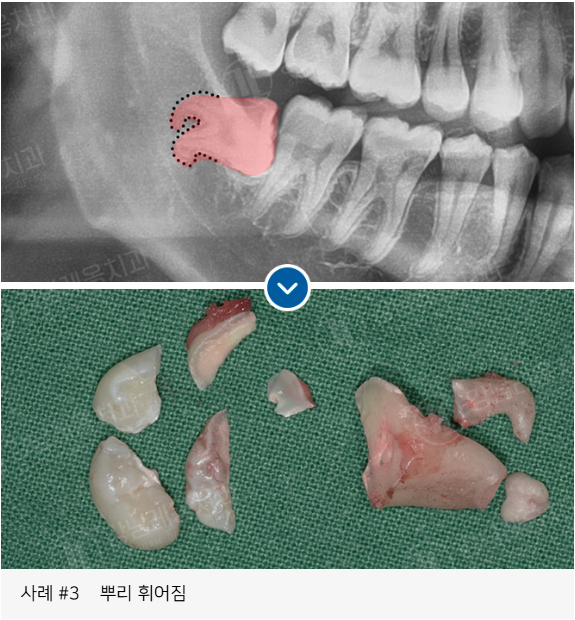

✅ 뿌리가 휘어있거나 여러갈래로 나뉜 사랑니

고난도 케이스 경험 다수

사랑니 발치로 강남레옹치과에 방문해주시는

아래와 같은 고난도 케이스도

충분한 상담을 통해

사랑니 진료를 진행하고 있습니다.